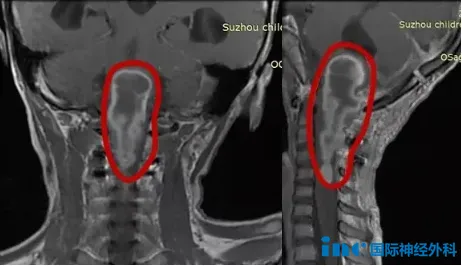

头颅磁共振成像(MRI)发现:第四脑室下方-枕大孔区-上段颈椎椎...